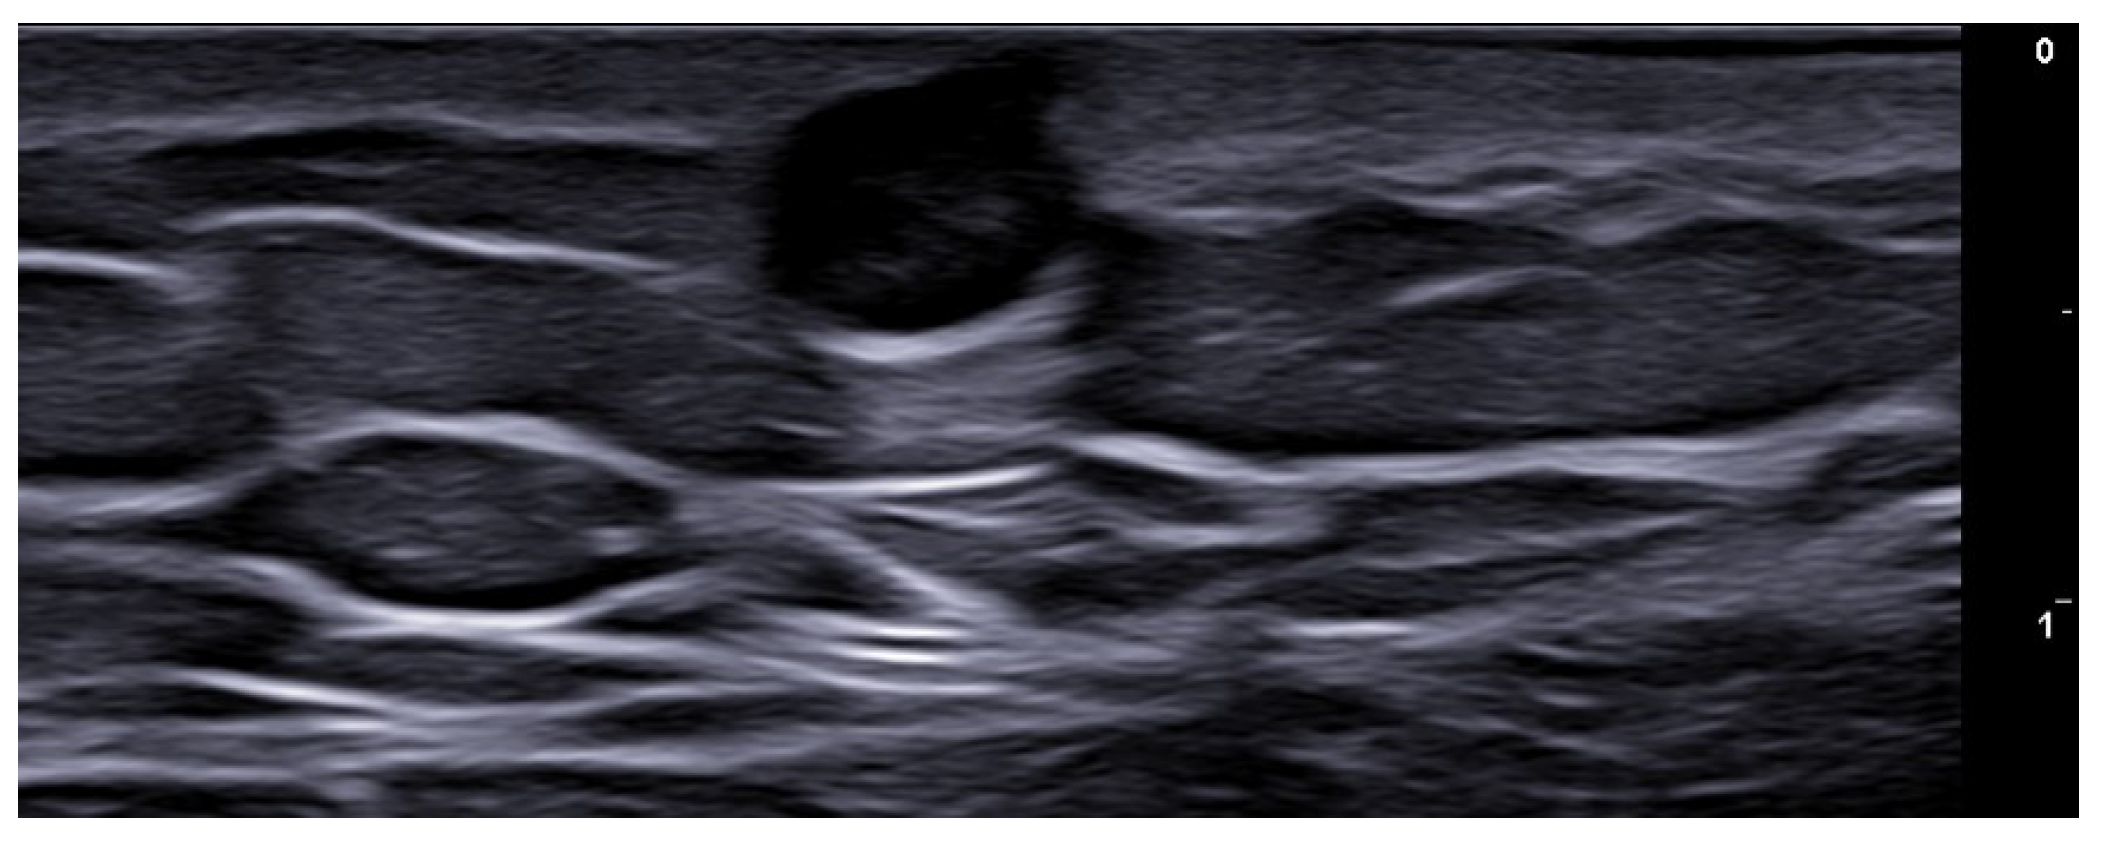

- Dini, V.; Michelucci, A.; Granieri, G.; Zerbinati, N.; Margiotta, F.M.; Romanelli, M. Evaluation of post-surgical complications of hidradenitis suppurativa lesions explored with presurgical ultra-high frequency ultrasound mapping. J. Wound Care 2024, 33, S10–S16. [Google Scholar] [CrossRef]

- Michelucci, A.; Fidanzi, C.; Manzo Margiotta, F.; Granieri, G.; Salvia, G.; Janowska, A.; Romanelli, M.; Dini, V. Presurgical Mapping with Ultra-high Frequency Ultrasound of Hidradenitis Suppurativa Lesions Treated with Wide Local Excision and Secondary Intention Healing. Dermatol. Surg. 2025, 51, 36–39. [Google Scholar] [CrossRef]